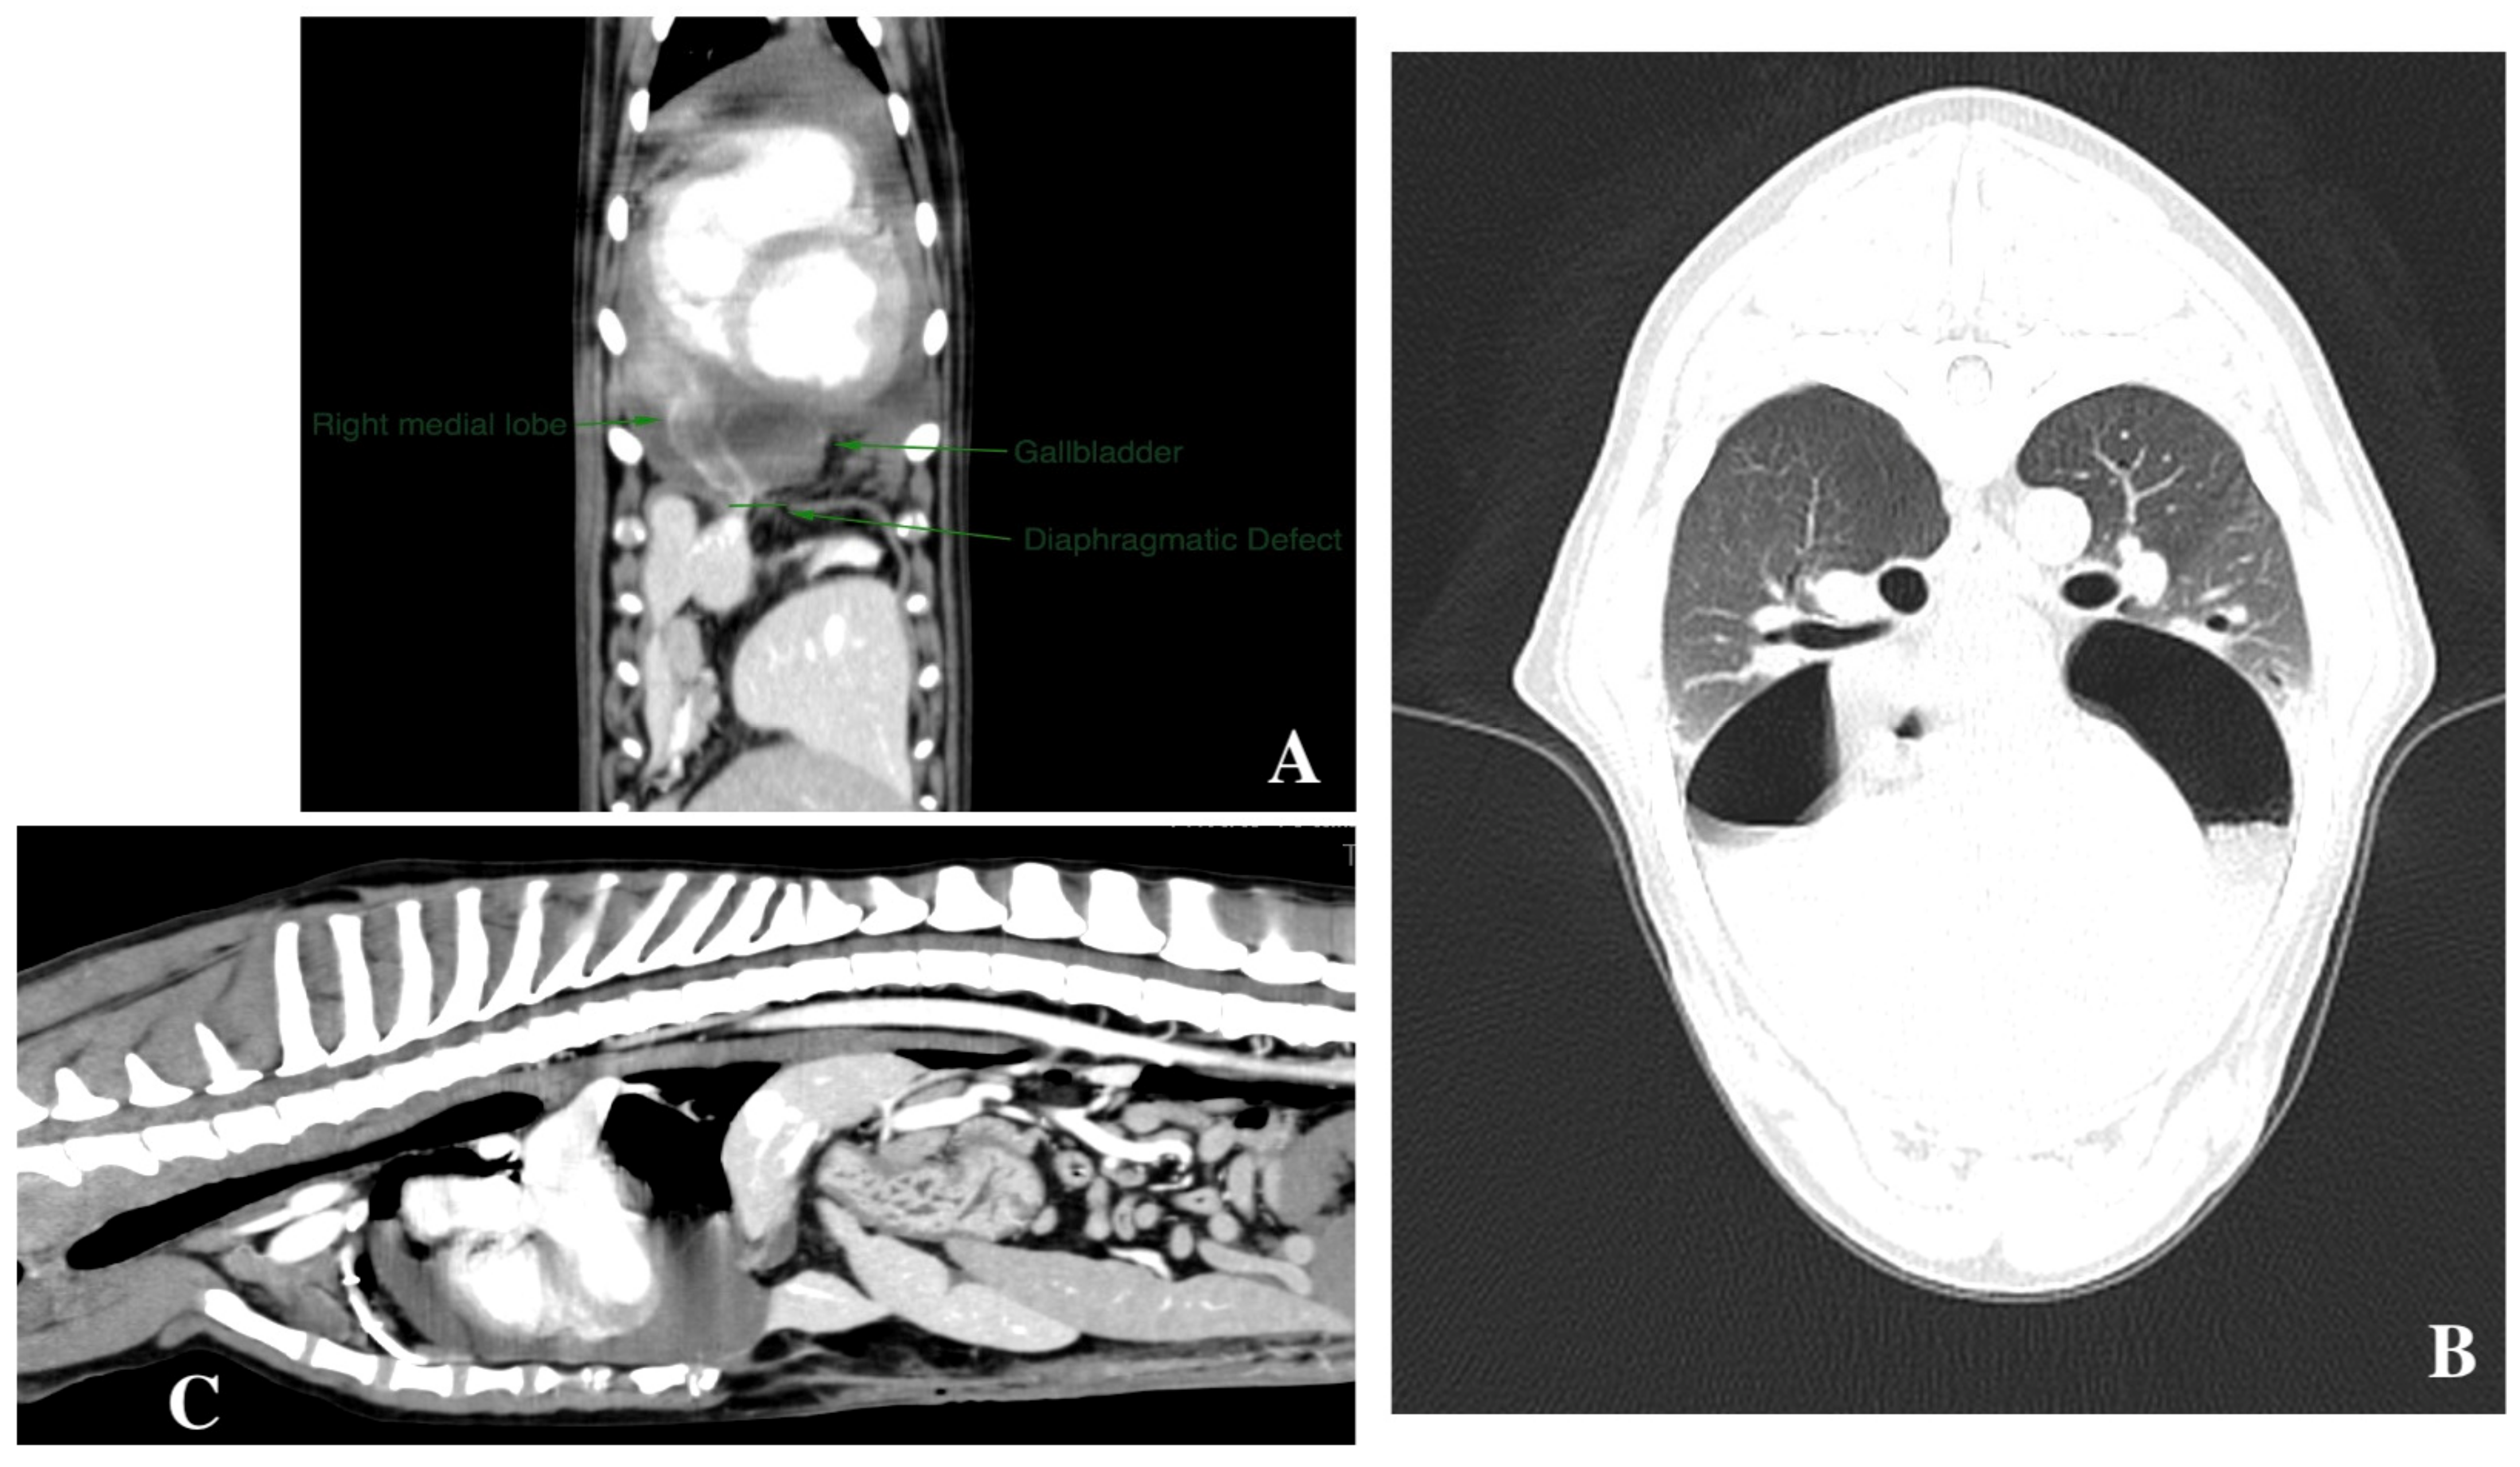

2.2. Diagnostic Imaging